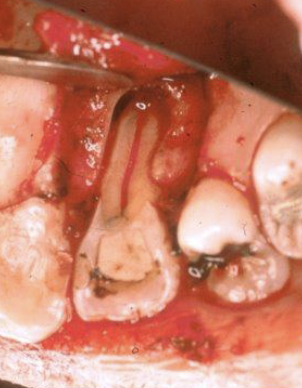

What is the anatomical variation in this lateral incisor?

Lingual developmental or palato-radicular groove

Dens invaginatus

Talon cusp